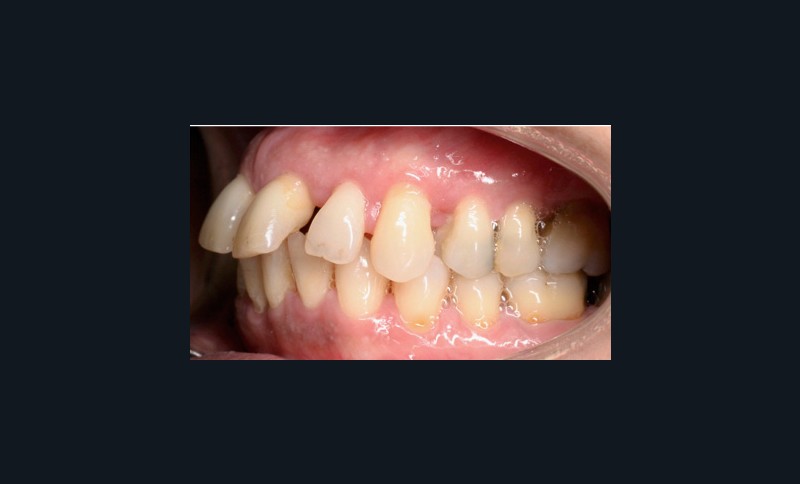

À l’examen endo-buccal (fig. 2), on note une formule dentaire complète (absence des 8) avec présence de restaurations multiples étanches, un bon contrôle de plaque et une parodontite de stade 4 grade C stabilisée [3], des récessions gingivales et des mobilités dentaires généralisées (degré 2, classification de Miller). L’arcade mandibulaire présente une courbe de spee importante avec égression du bloc incisivo-canin. Les milieux inter-incisifs sont alignés, le recouvrement est normal, le surplomb est augmenté à 3 mm et associé à des diastèmes et de la vestibulo-version des incisives maxillaires. Les relations antéro-postérieures canine et molaire sont en Classe I d’Angle.